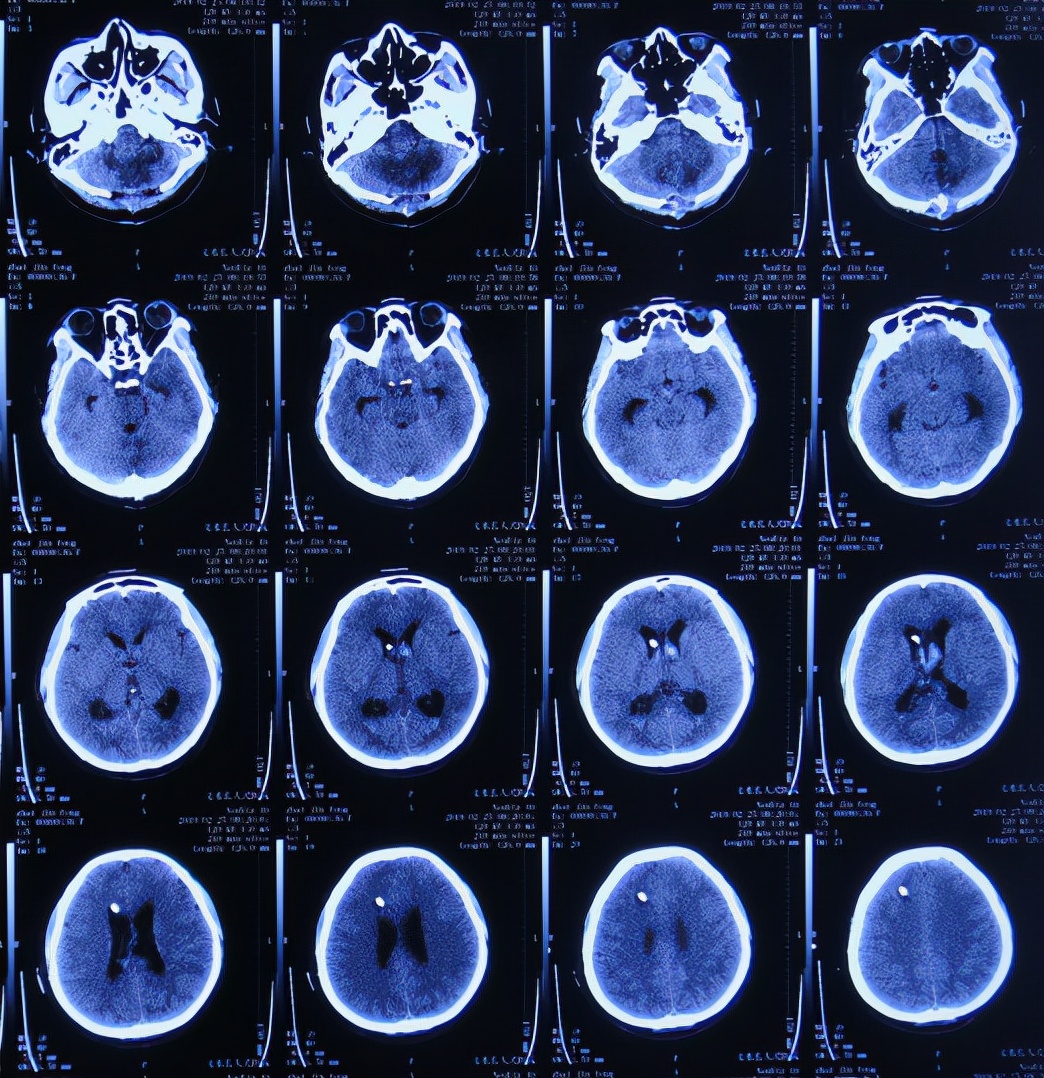

患者2019年2月18日下午,睡觉时突然出现剧烈头痛,持续无缓解,于是就诊于当地的山西省文水县某医院,查头颅CT示小脑出血破入脑室( 图-1 );考虑出血量不多,住院保守治疗。

图-1: 2019年2月18日头颅CT

但1小时后出现意识障碍加重,复查头颅CT( 图-2 )示小脑出血增多,急诊进行了左侧脑室穿刺外引流术+后颅窝血肿清除;术后住入重症监护室。

图-2: 2019年2月18日头颅CT02